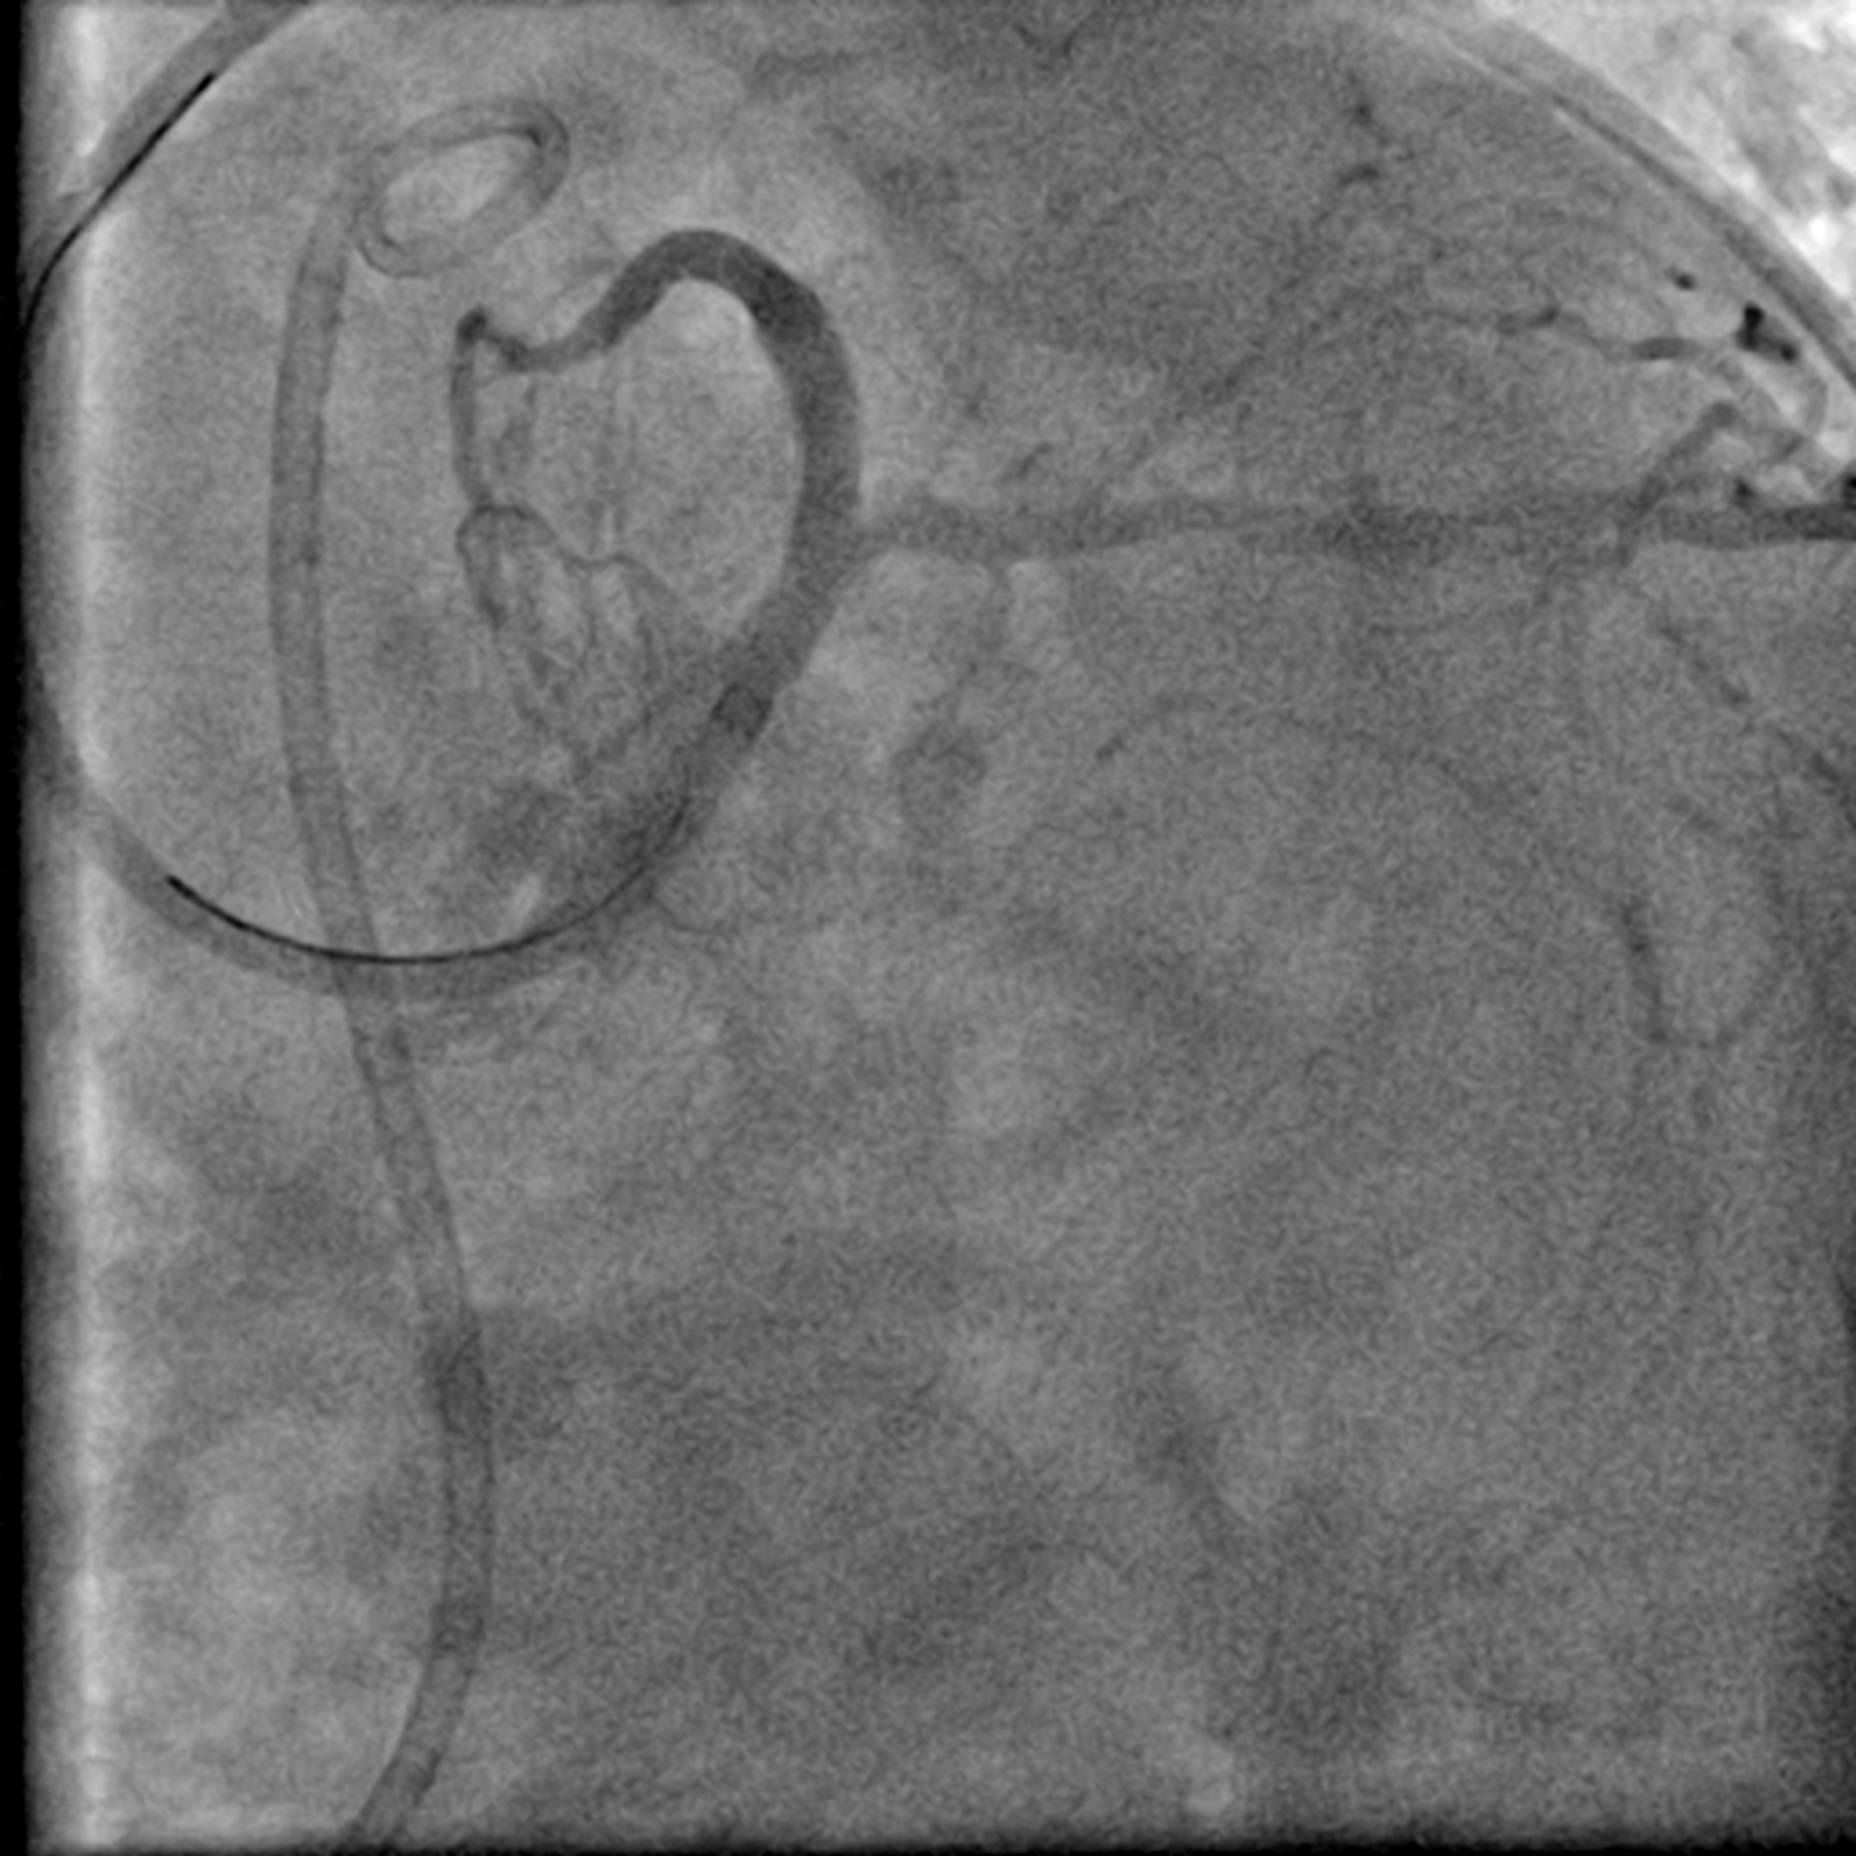

Coronary angiogram showed a Left Main Stem (LMS) bifurcation lesion (Medina 0,1,1) with visible calcification in the proximal left anterior descending artery (LAD). IVUS confirmed severe calcification in the proximal LAD and a calcified nodule causing significant occlusion at the left circumflex artery (LCx) ostium. The right coronary artery (RCA) was spared. Due to severe calcification, a calcium debulking device was required, and the decision was made to proceed with Orbital Atherectomy (OAS).

After positioning the ViperWire in the distal LAD, the OAS was delivered, and calcium debulking at low speed was performed safely. Afterward, the LAD was pre-dilated with a 2.5 mm scoring balloon and a 3.5 mm cutting balloon, while the LCx was pre-dilated with a 3.0 mm cutting balloon. A repeat angiogram revealed an Ellis 3 perforation in the proximal LAD, accompanied by a drop in the patient's blood pressure. Expeditiously, a 3.0 mm balloon was inflated at the perforation site, and its location was confirmed with an angiogram, which indicated immediate reduction of the perforation. A pigtail catheter was inserted simultaneously under echocardiographic guidance, and autologous blood transfusion was initiated. The perforation was covered with a 2.5 mm x 20 mm covered stent and post-dilated with a 3.0 mm NC balloon. This reduced the leak, but significant flow persisted. IVUS showed a gap between the stent strut and vessel wall near the LAD carina, allowing for persistent leakage. The covered stent was further post-dilated with a 3.5 mm NC balloon and a hugging balloon technique using two 2.5 mm balloons. These measures failed, as the maximal expansion of the 2.5 mm covered stent is limited to 3.0 mm. A Kissing Balloon Technique (KBT) was attempted at the bifurcation, but it proved futile. Finally, a second 3.5 mm covered stent was placed proximally, which successfully sealed the perforation, leaving only a trivial leak. The hemoperricardium resolved after 24 hours.